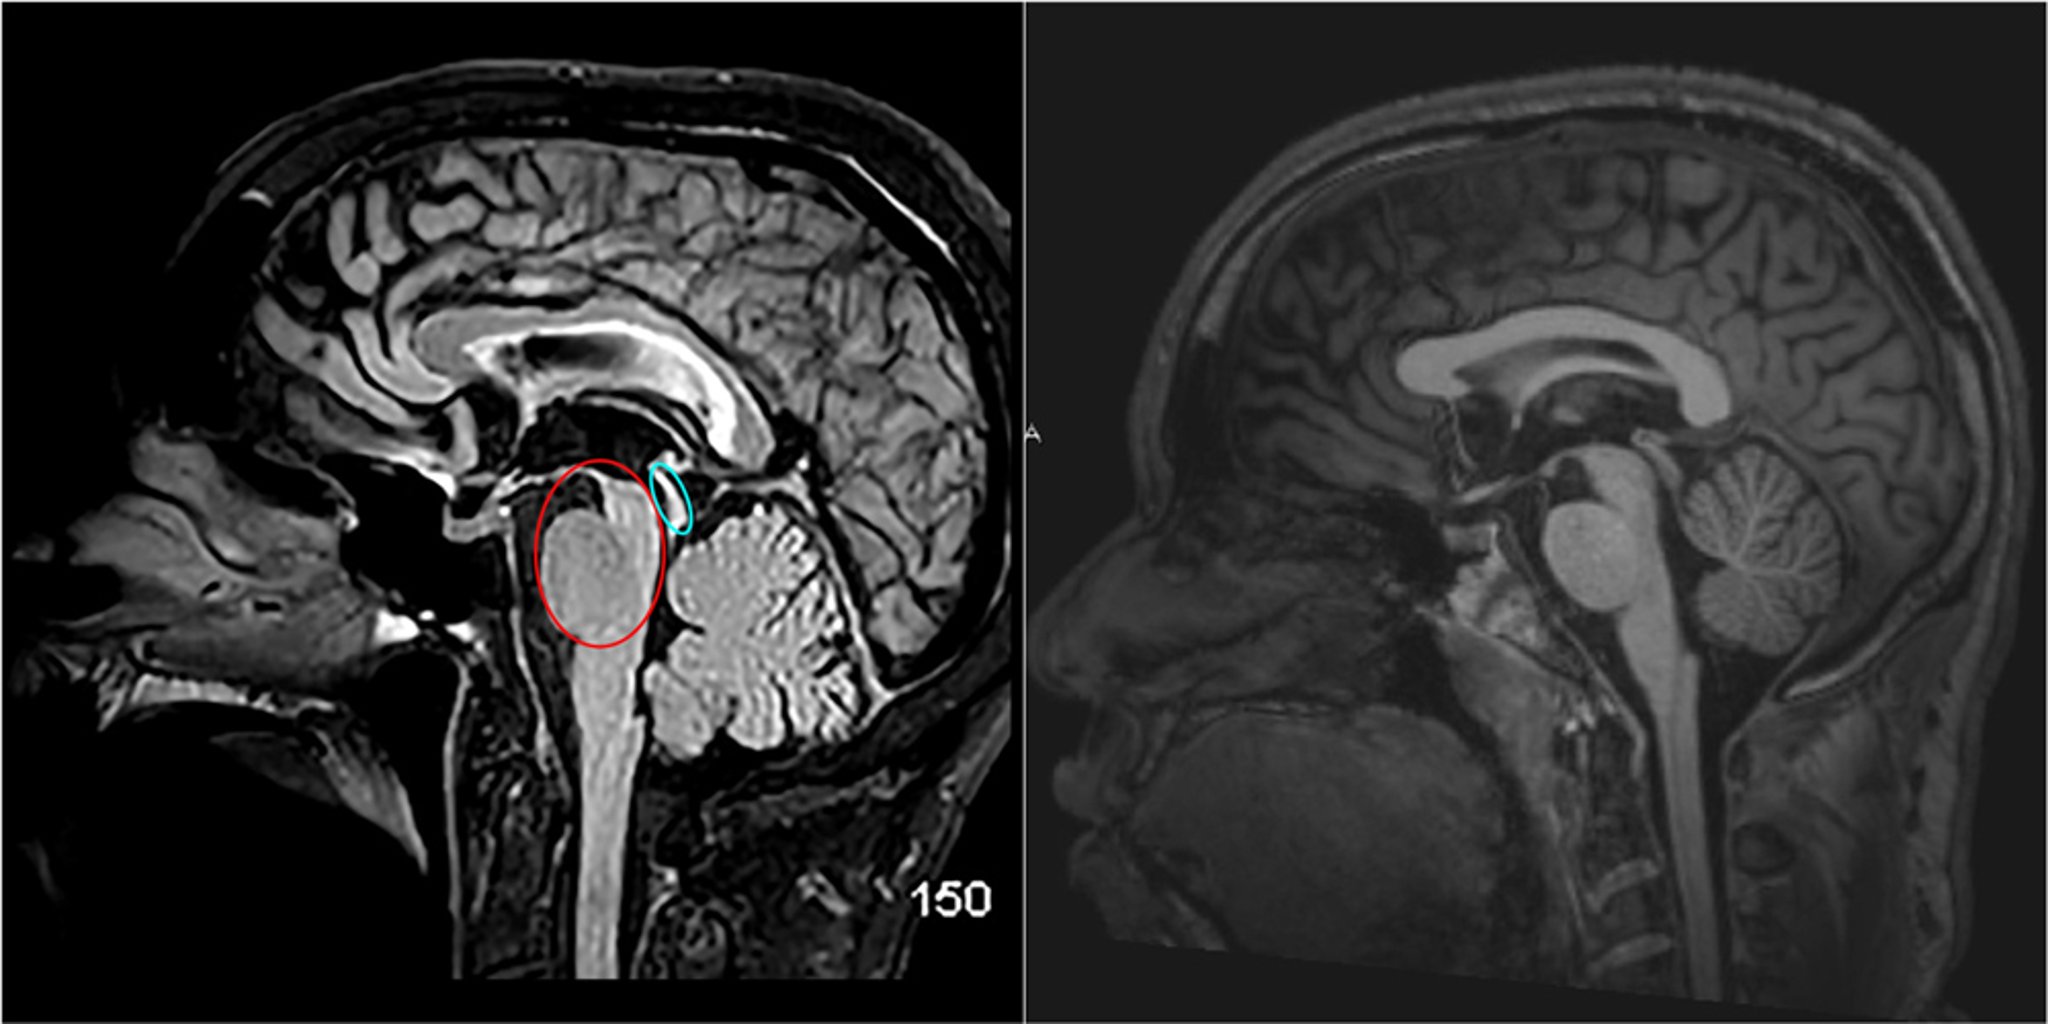

Progressive Supranuclear Palsy (MRI)

This sagittal T2-FLAIR (fluid-attenuating inversion recovery) MRI scan (left) shows typical findings in progressive supranuclear palsy (one of the Parkinson plus syndromes) with prominent midbrain atrophy, resulting in the hummingbird sign (red circle), in addition to atrophy of the upper tectal plate (blue circle).

A normal sagittal MRI scan of the brain is shown for comparison (right).